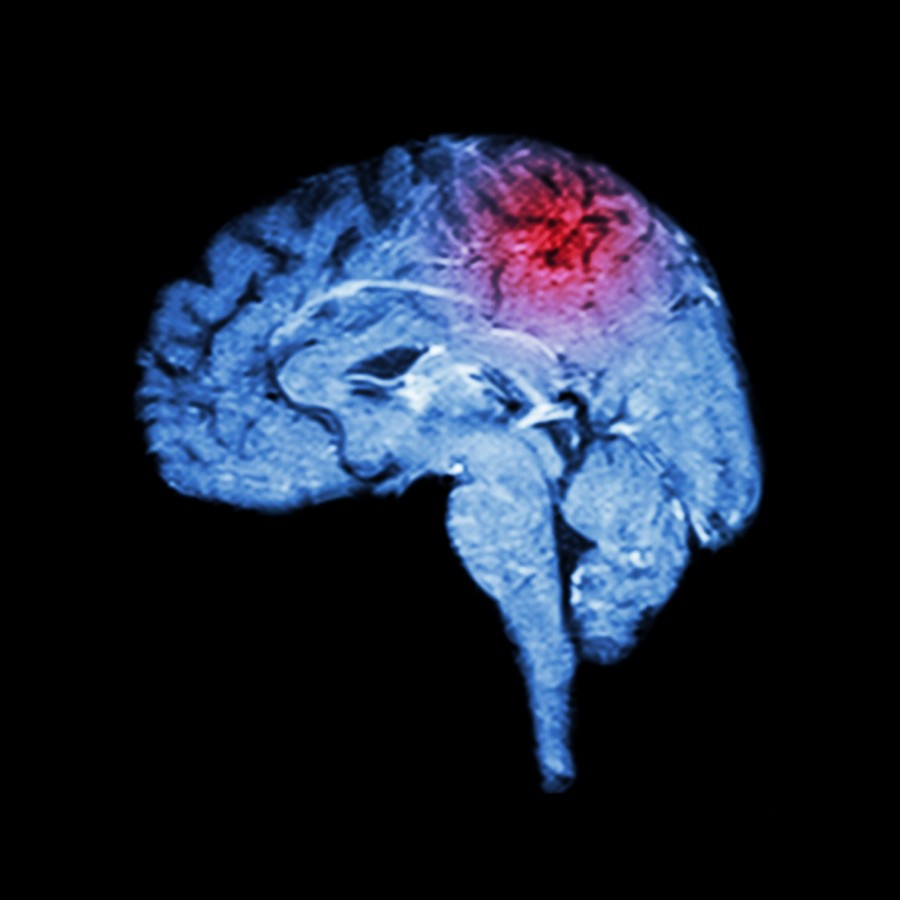

Stroke signs and symptoms to recognize

Spotting the signs and symptoms of a stroke early on can prompt a person to call 911 immediately, so that the treatment can begin right away to reduce to risk of complications or even death. The American Stroke Association has outlined five key signs of stroke that should urge someone to call 911 right away. ...click here to read more